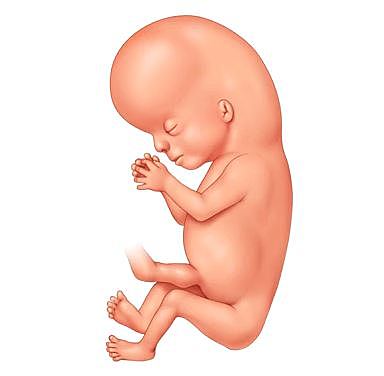

• Caracterización

35

Caracterización

El embrión ya tiene características humanas evidentes